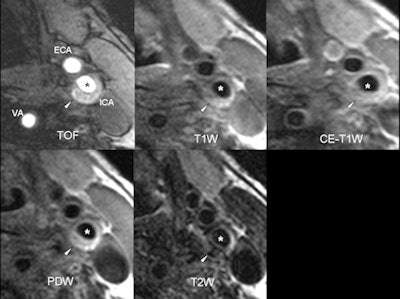

| Axial MR images of an 82-year-old symptomatic patient without cardiovascular risk factors. The patient suffered a stroke ipsilateral to the left carotid artery five days before the MRI examination. The arrowhead points to a complicated eccentric plaque that is hyperintense on time-of-flight (TOF) and T1-weighted images, indicative of intraplaque hemorrhage. Of note, no luminal stenosis in the ICA (asterisk) can be seen. The images illustrate that cerebrovascular events due to macroangiopathic carotid disease can occur in the absence of luminal stenosis. ICA = internal carotid artery, ECA = external carotid artery, VA = vertebral artery, PDW = proton density-weighted image. (Provided by Dr. Tobias Saam) |